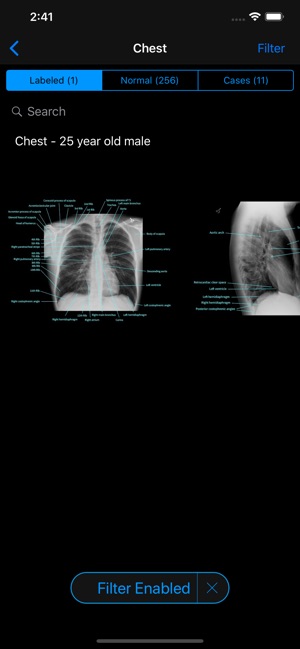

• 2000+ high resolution x-rays spanning patients of all ages (all x-rays have been read by board-certified radiologists)

• Filter studies by patient age, gender, body region, study, diagnosis, and lateralization